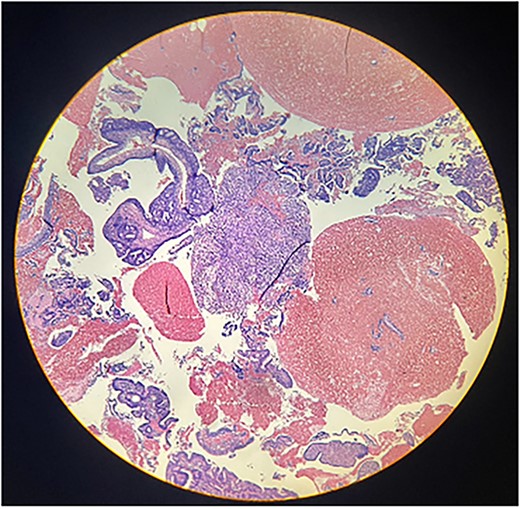

Macroscopically, an amorphous uterus weighing 397 g and measuring 12 × 9 × 7.5 cm with a brown serosa, and multinodular violaceous areas was examined. When incised, the endometrial cavity was occupied by a whitish polypoid mass of 8 × 5 cm which invaded the myometrium. In addition, multiple firm whitish nodules ~2 × 1.5 cm in diameter were identified. Bilateral ovaries and fallopian tubes appeared to be of normal morphology and size. Histologically, there was evidence of epithelial and sarcomatous components (Figs 1 and 2), and the epithelial component developed atypical glands (Fig. 3). The diagnosis of MMMT was given due to histologic findings.

Photomicrograph shows the presence of a malignant mixed tumor containing epithelial and sarcomatous components (H&E stain ×4).